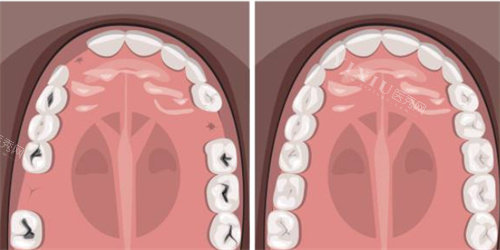

首先,牙齿龋坏程度是一个重要因素。如果牙齿龋坏面积过大,剩余的健康牙体组织就会比较少,这会导致补牙材料缺乏足够的支撑和固位力。

就像一座大厦,如果根基不稳,上面的建筑就容易倒塌。当牙齿龋坏重的时,即使医生技术再好,补牙材料也可能因为没有稳固的基础而频繁脱落。

那么,当补牙材料频繁脱落时该怎么办呢?患者应该及时复诊,向医生详细描述情况。医生会根据具体情况进行评估,如果是牙齿龋坏重的导致的,可能需要采取更复杂的修复方法,如做牙冠;